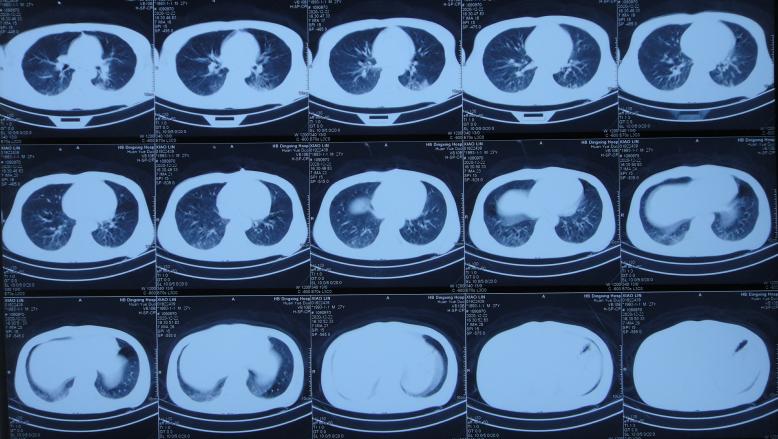

开颅术后10天即2020年12月22日(腰大池引流6天后),腰大池引流期间无发热,因脑脊液颜色血色转为黄色,给予拔除腰大池引流管;但查头颅CT示仍有脑膨出,且脑室有稍增大( 图-5 ),肺部CT认为有点感染( 图-6 )。

图-6: 2020年12月22日肺部CT